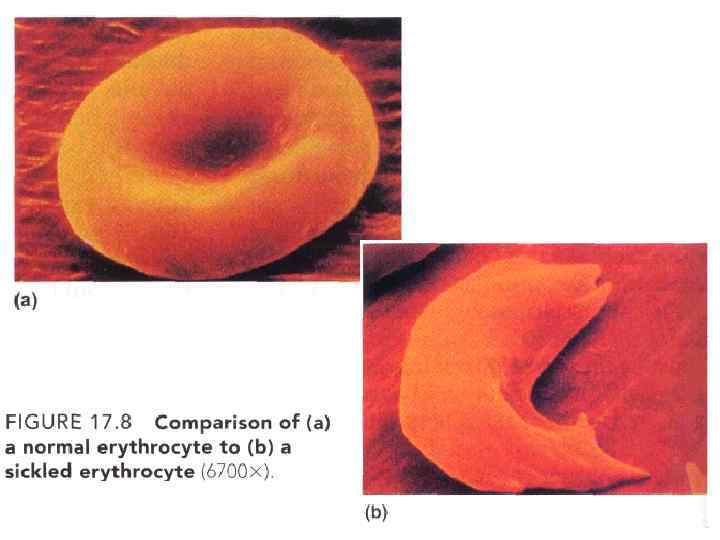

• Эритроциты в крови здорового человека преимущественно (до 70 %) имеют форму двояковогнутого диска. • Поверхность диска в 1, 7 раза больше, чем поверхность тела такого же объема, но сферической формы.

• Эритроциты в крови здорового человека преимущественно (до 70 %) имеют форму двояковогнутого диска. • Поверхность диска в 1, 7 раза больше, чем поверхность тела такого же объема, но сферической формы.

Материал для исследования: венозная или капилярная кровь. Кровь берется с ЭДТА • Определение количества эритроцитов проводят в счетной камере и с помощью счетчиков или анализаторов клеток крови. • Используя так называемое “правило трех”, можно по количеству эритроцитов (RBC) оценить концентрацию гемоглобина и показатель гематокрита. 3*RBC = Hb 3*Hb = Ht • Эту зависимость можно использовать для оценки параметров крови, но только в тех пробах, где эритроциты имеют правильное строение.

Материал для исследования: венозная или капилярная кровь. Кровь берется с ЭДТА • Определение количества эритроцитов проводят в счетной камере и с помощью счетчиков или анализаторов клеток крови. • Используя так называемое “правило трех”, можно по количеству эритроцитов (RBC) оценить концентрацию гемоглобина и показатель гематокрита. 3*RBC = Hb 3*Hb = Ht • Эту зависимость можно использовать для оценки параметров крови, но только в тех пробах, где эритроциты имеют правильное строение.